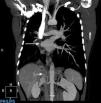

En la radiografía de tórax se aprecia una resolución de la imagen de condensación junto con disminución del volumen de pulmón derecho con desviación de mediastino hacia ese lado. La TAC realizada se muestra en la figura 1. Se realiza una broncoscopia con los siguientes hallazgos: ausencia de bronquio lobar superior derecho, existiendo en su lugar la salida de 2 bronquios accesorios que no dejan pasar el broncoscopio. Tampoco se aprecia la salida del bronquio apical y paracardiaco del lóbulo inferior derecho. La espirometría revela un patrón restrictivo moderado y el ecocardiograma una estenosis aortica ligera sin datos de hipertensión pulmonar.

Por último, se realiza una angiografía que confirma todos los hallazgos descritos en la TAC y, además, muestra que parte del sistema de colaterales formadas para nutrir pulmón derecho proviene de una arteria subfrénica inferior (fig. 1).